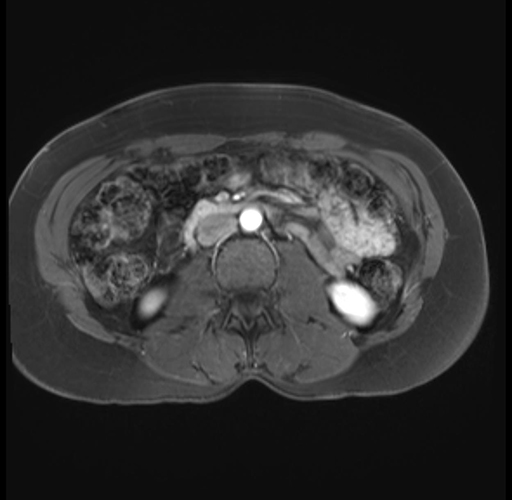

Imaging Analysis

Look through the patient's CT scan to identify any areas of concern for the necessary procedure.

Based on your CT findings, which issue(s) are present and would give reason for "planned slowing down moment(s)" in this case?